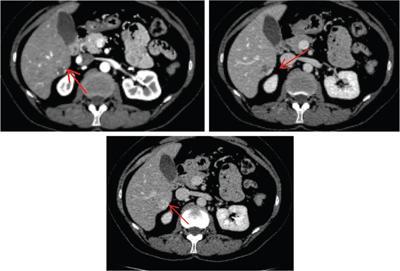

Shrinivas B. Desai, Ritu K. Kashikar, Shreya Shukla Radiological signs are classical and distinctive abnormalities characteristic of a disease. These can be seen on any imaging modality. Resemblance to commonly seen objects and patterns form the basis of radiological signs. The aim is to help the reader associate, understand and memorize these pathologies with the aid of signs. Various signs pertinent to hepatobiliary system are described in the chapter. Described on MRI when liver lesion shows a peripheral rim of high T2 signal intensity with the centre of the lesion appearing isointense to the background of noncirrhotic liver on T2WI mimicking an atoll. It is considered a characteristic sign of an inflammatory hepatic adenoma (image) but is only seen in about one-third of cases Extrinsic smooth impression over medial aspect of duodenum along its posteroinferior aspect, seen in pancreatic head pathologies like carcinoma. This sign is seen in pancreatic adenocarcinoma Presence of a persistently hyperattenuating dot within a lesion on arterial and portal venous CT. This corresponds with peripheral nodular enhancement seen on dynamic MR. Presence of bright dot suggests that the lesion is a hemangioma and helps in ruling out metastasis Ultrasound appearance of multiple cystic spaces or lesions that has been used to describe the appearance of an intraductal papillary mucinous neoplasm of the pancreas. Seen on contrast CT in portal hypertension. The appearance is based on resemblance to Medusa from Greek mythology. Dilated engorged paraumbilical veins radiating across umbilicus to join systemic veins is seen. This sign is seen in Caroli’s disease on contrast CT. Enhancing dots within dilated intrahepatic bile ducts represent portal radicles. Caroli’s disease Irregularly dilated pancreatic duct with multiple strictures and intervening dilatation with associated dilated side ductules resemble multiple lakes supplied by a single territory. Best seen in MRCP images. Chronic pancreatitis It is a finding on MRI and CT and is best seen on MRI T2-weighted and postcontrast T1-weighted sequences. Small necrotic/purulent areas in the pyogenic abscess ‘cluster’ together and then coalesce into a larger necrotic/purulent areas, eventually becoming a larger septated abscess cavity. At the periphery of these clusters: Associated with pyogenic hepatic abscesses and can help differentiate pyogenic abscesses from other types of liver lesions Abrupt termination of gas within the proximal colon at the level of radiological splenic flexure. The inflammatory exudates in pancreatitis extend to the phrenicocolic ligament giving rise to this sign Seen on grey scale ultrasound as a reverberation artifact when small calcific or highly reflective objects are imaged. The colour comet-tail artifact is an ultrasonographic sign seen in a number of situations when colour Doppler scanning is performed. This sign occurs in cases of traumatic right-sided diaphragmatic rupture with resultant partial herniation of liver through the defect. Separation of the herniated liver from its intra-abdominal component is via a small constriction at the level of diaphragm resembling a cottage loaf. Cottage loaf is a particular shape of bread in which larger and smaller roughly spherical balls are squashed together. Traumatic right-sided diaphragmatic rupture with resultant partial herniation of liver Bile eccentrically outlines luminal stone, creating a low attenuation crescent. Best seen on MRCP images. Choledocholithiasis Dilatation of both pancreatic duct and CBD is referred to as the double duct sign. Positive double duct sign suggests the diagnosis of carcinoma of the head of the pancreas and ampullary tumours and is hence considered ominous. Occasionally the sign may be seen in impacted gallstone in the distal duct. This feature is seen in patients with liver abscess on contrast-enhanced CT. A double, inner hyperattenuating and outer hypoattenuating rim is seen surrounding the hypodense abscess. The inner hyperattenuating rim corresponds to the enhancing abscess membrane, while the outer rim corresponds to the edema of the surrounding liver which appears hypodense and may show delayed enhancement. Liver abscess A positive duct penetrating sign is when a mass is penetrated by an unobstructed pancreatic duct; this makes focal pancreatitis the most likely cause rather than pancreatic carcinoma. This sign is best appreciated on MRCP (or ERCP). A radiographic sign that can be useful in differentiating between focal pancreatitis (inflammatory pancreatic mass) from pancreatic carcinoma. The duct-penetrating sign on MRCP is more helpful in differentiating between these two entities than a delayed enhancement pattern on CT or MRI It occurs when there is both limy bile and a gallstone in the common bile duct. The linear vertical radiopaque bile forms the line of the exclamation mark (i.e. !), whilst a more distal calculus forms the ‘dot’ at the end of the exclamation mark. Pathognomonic imaging sign of the rare diagnosis of limy bile on plain abdominal radiography Nonenhancing ruptured lesion with peripheral rim enhancement showing discontinuity from the rest of the liver and protruding from the liver surface is called the enucleation sign. Ruptured HCC Enlargement of the pericholecystic space. One of the signs of liver cirrhosis Can be seen on technetium 99m sulphur colloid scans of the liver and spleen, as well as CT studies. It occurs as a focal area of increased radiopharmaceutical uptake in the medial segment of the left hepatic lobe (segment IV) occurring as a result of SVC obstruction and portosystemic venous shunting between the superior vena cava and the left portal vein via the internal thoracic and paraumbilical veins. The equivalent of this sign may also be seen on contrast-enhanced CT scans as a hypervascular region. Budd–Chiari syndrome causes the hot spot sign in the caudate lobe

9) Cluster sign